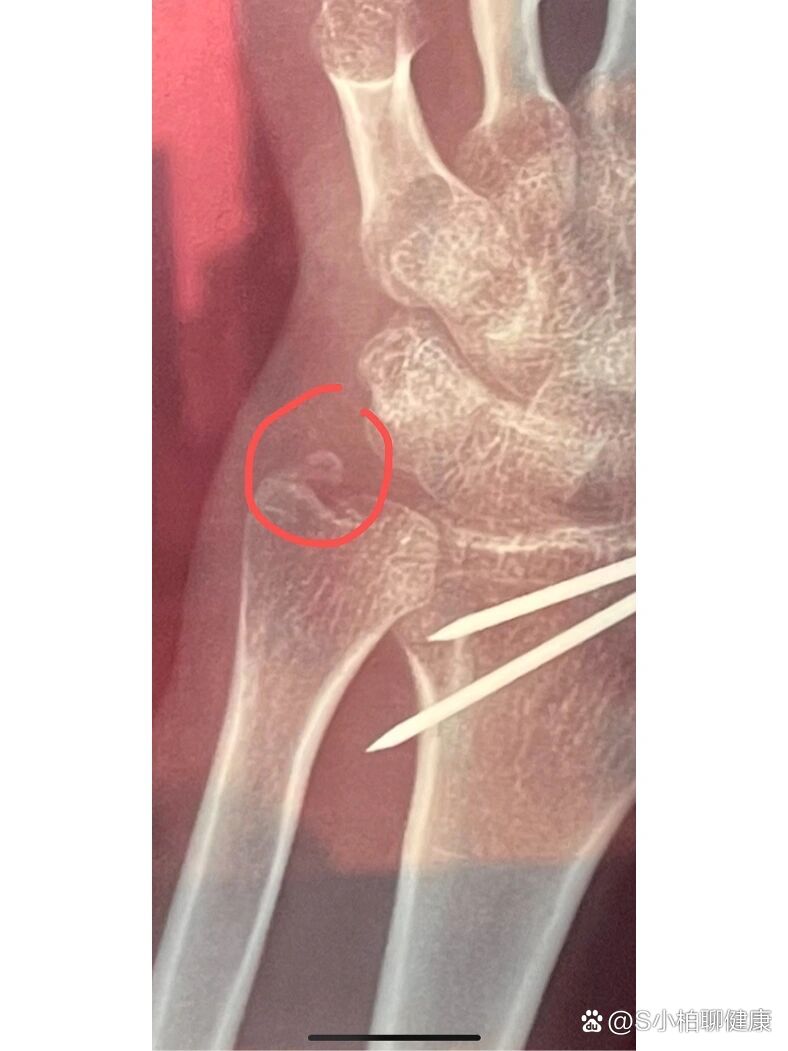

右侧桡骨远端及尺骨茎突粉碎性骨折;右腕钩

图片尺寸1280x1706